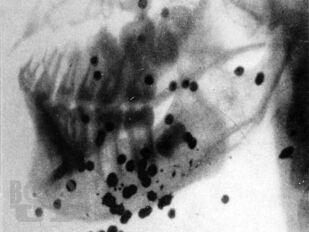

Пособие посвящено актуальной проблеме травматических повреждений мягких тканей челюстно-лицевой области. Дана классификация, статистика и характеристика повреждений, связанных с особенностью строения и функциональности данной области. Описана клиническая картина и способы лечения огнестрельных и неогнестрельных травматических повреждений мягких тканей на достационарном этапе (в поликлинике и при транспортировке) и в стационаре. Представлены характеристика и лечение травматических повреждений мягких тканей различных отделов челюстно-лицевой области. Описаны осложнения, связанные с данной патологией, способы питания больных, уход за полостью рта, лечебная гимнастика и физиотерапия.